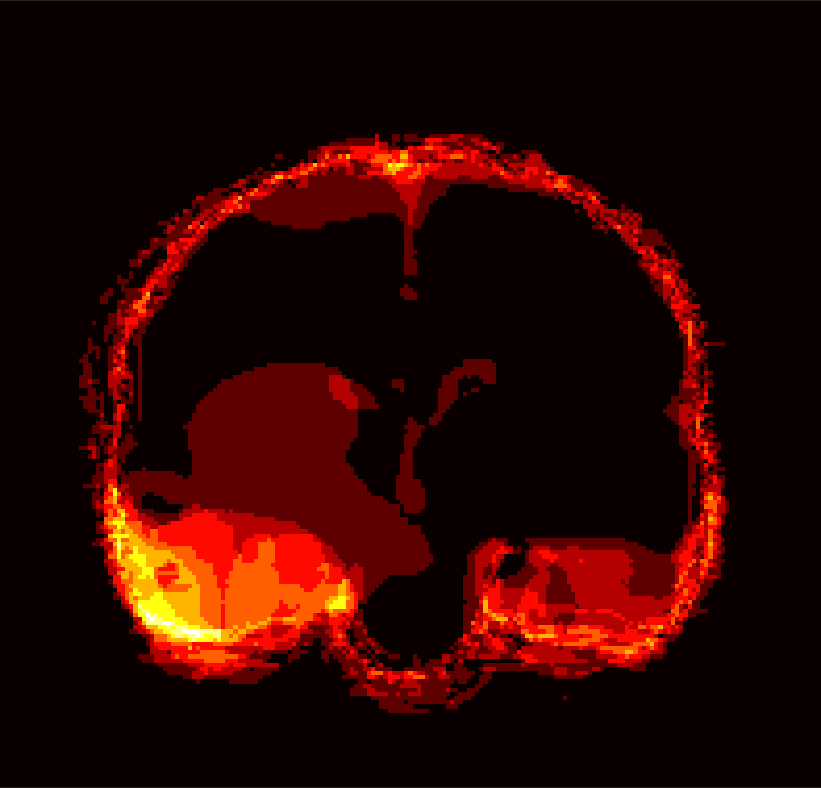

Fig. 1 shows example images from each dataset to illustrate image variability. IBSR and LPBA40 contain images from normal subjects and include large portions of the neck; BRATS has very low out-of-plane resolution; and the TBI dataset contains large pathologies and abnormal skulls.

Refer to caption

Figure 1: Illustration of image appearance variability on a selection of images from each (evaluation) database. From top to bottom: IBSR, LPBA40, BRATS and TBI.